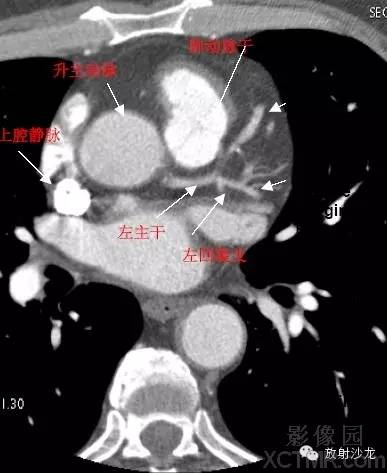

A.Aorta-Ascending Aorta升主动脉

D. Aorta-Descending Aorta降主动脉

SVC –Superior Vena Cava上腔静脉

PA -Pulmonary Artery肺动脉

LMA -Left Main Artery冠状动脉左主干

LCX -Left Circumflex Artery左回旋支